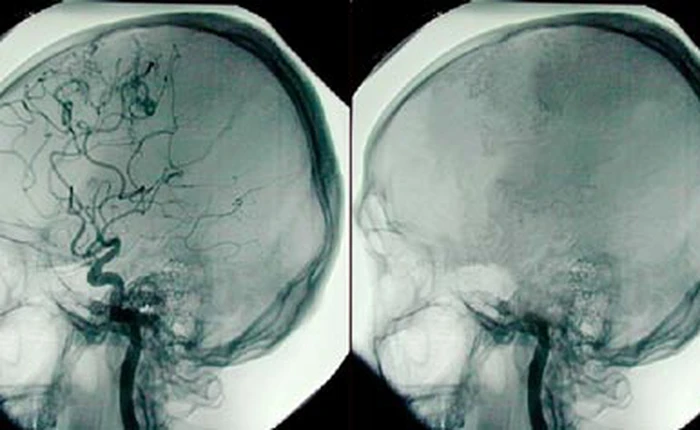

(GenK.vn) - Não là một trong những bộ phận quan trọng nhất của con người, liệu con người có thể sống mà không có não?